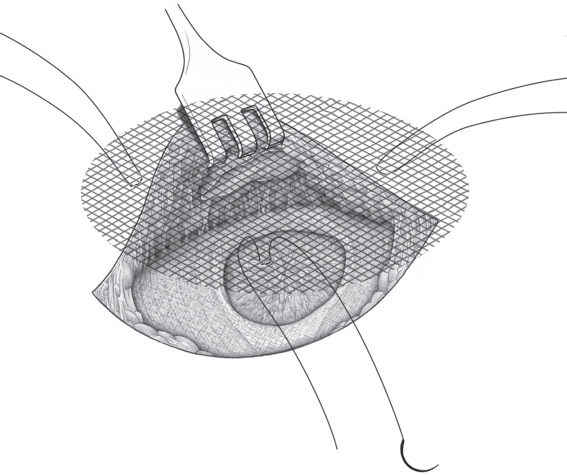

If a femoral hernia is found in addition during open surgery, TIPP repair can be used without slitting the mesh laterally (see section

2.3.2) or the Lichtenstein repair can be modified by fixing the medial part of the mesh to the Cooper ligament rather than to the inguinal ligament (

Fig. 3.3). Suture of the mesh starts as usual over the pubic bone, without picking up the periosteum. From there, the suture passes from medial to lateral between the Cooper ligament and the inferior border of the mesh as far as the femoral vein. The suture ascends here to the base of the inguinal ligament and continues beyond the deep inguinal ring, as in men. The mesh is fixed cranially by the usual method of tying it loosely to the internal oblique muscle. At the deep inguinal ring, the proximal stump of the round ligament can be fixed to the mesh.

Fig. 3.3 Lichtenstein repair of a combined hernia with a femoral hernial orifice. Schematic cross-section of mesh position medial to the femoral vein.